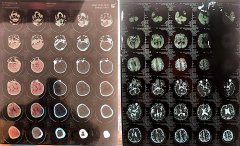

本站讯 2022年6月末,吉林省德惠市人于某波向记者爆料:他母亲吴某苓因左侧手脚偏瘫,言语不清,于2022年5月14日到德惠市人民医院(简称德惠市医院)就诊,遭到该医院神经外科医生郝..